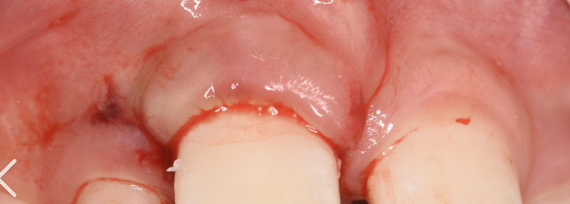

官方的通報裏,只說這些是誤入火場的野生動物。可參與清理的人,沒一個信這話。有個老法醫,後來跟家裏人喝多了纔敢說,他親手扒開過一具焦屍的嘴,裏面整整齊齊長着三十二顆人的牙齒,一顆不少,牙牀上還留着常年啃咬硬物磨出來的豁口。還有幾具骸骨,懷裏死死抱着啃了一半的人骨,旁邊還留着沒燒完的、發黑的胡蘿蔔。